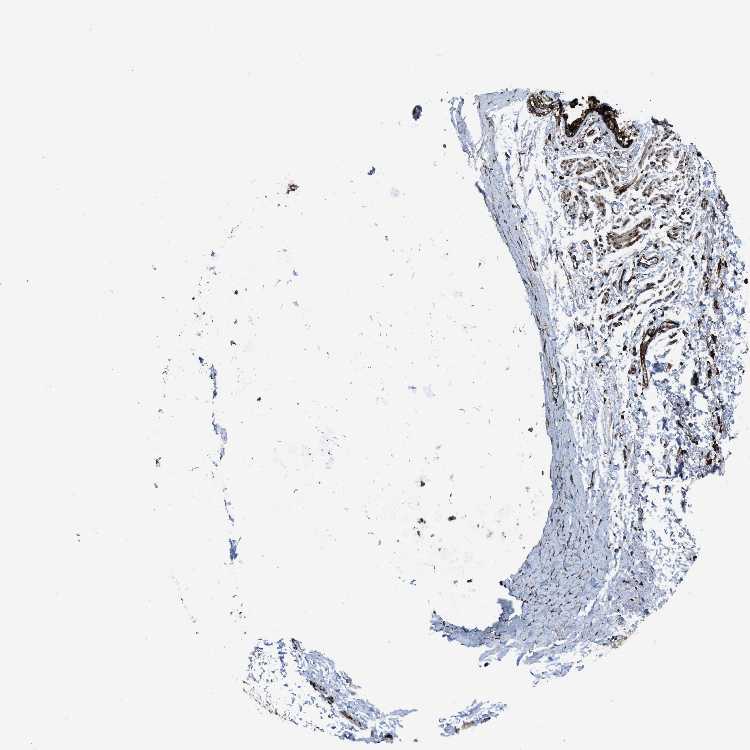

SOFT TISSUE 1 - Antibody stainingi

Antibody staining in the annotated cell types in the current human tissue is reported as not detected, low, medium, or high, based on conventional immunohistochemistry profiling in selected tissues. This score is based on the combination of the staining intensity and fraction of stained cells.

Each image is clickable and will lead to virtual microscopy that enables deeper exploration of all samples and also displays staining intensity scores, fraction scores and subcellular localization as well as patient and tissue information for each sample.

Antibody HPA018126Antibody HPA063617

Chondrocytes -High

Fibroblasts HighHigh

Peripheral nerve Medium-